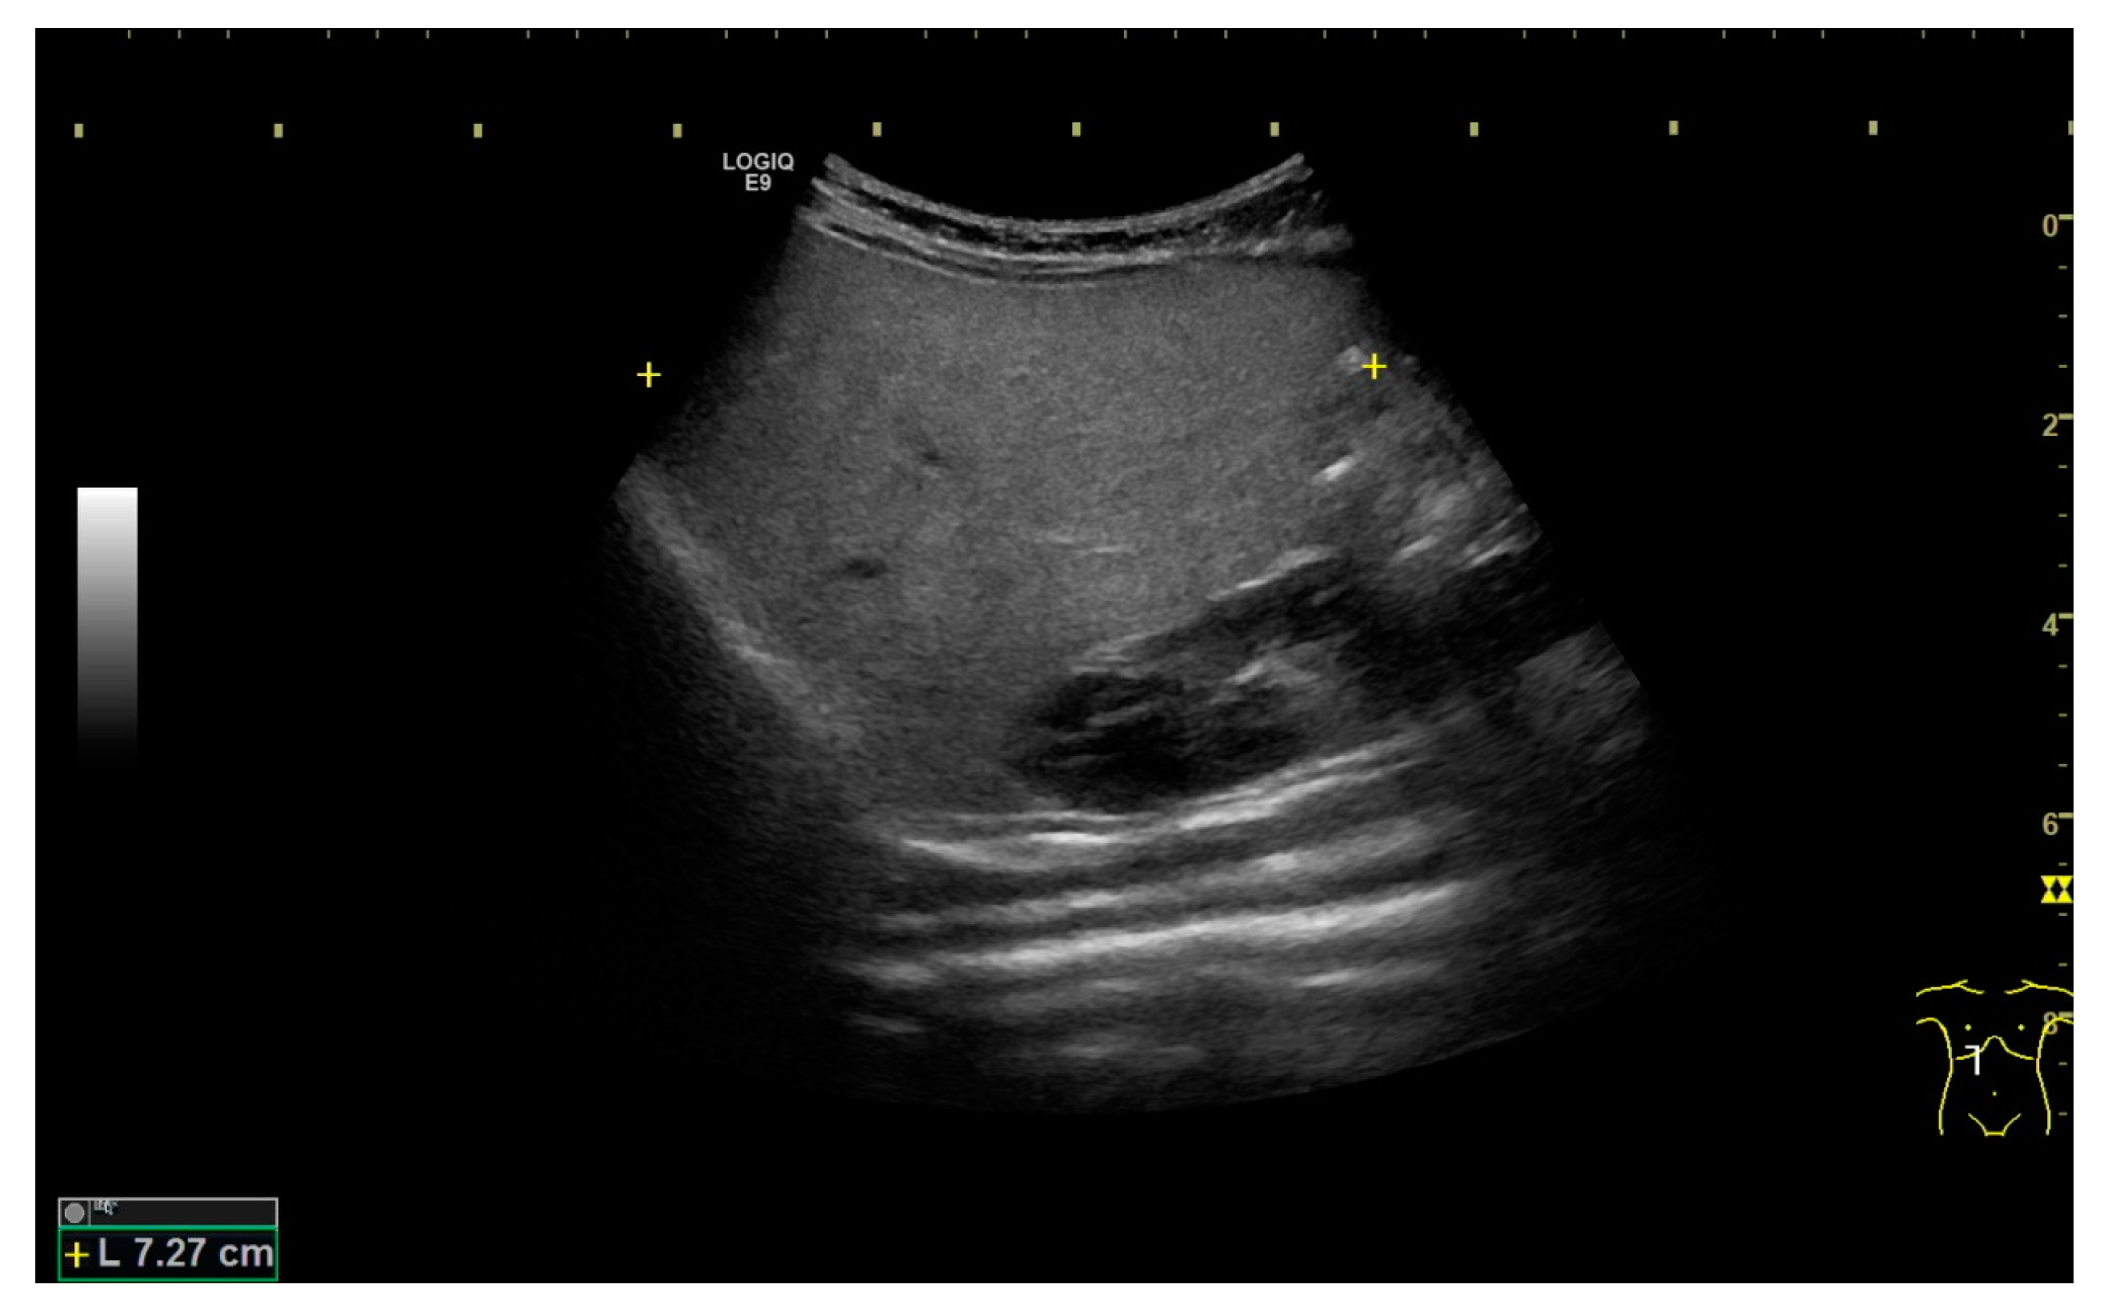

2. Case Presentation